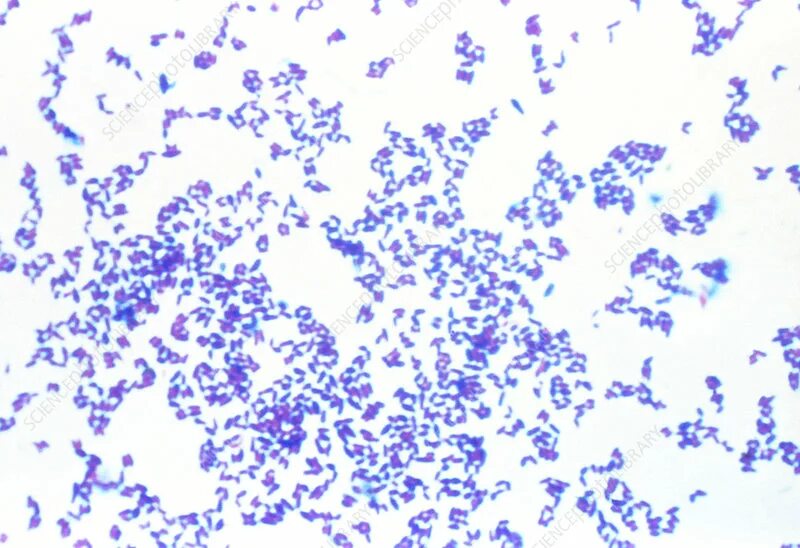

Corynebacterium spp в мазке у мужчин